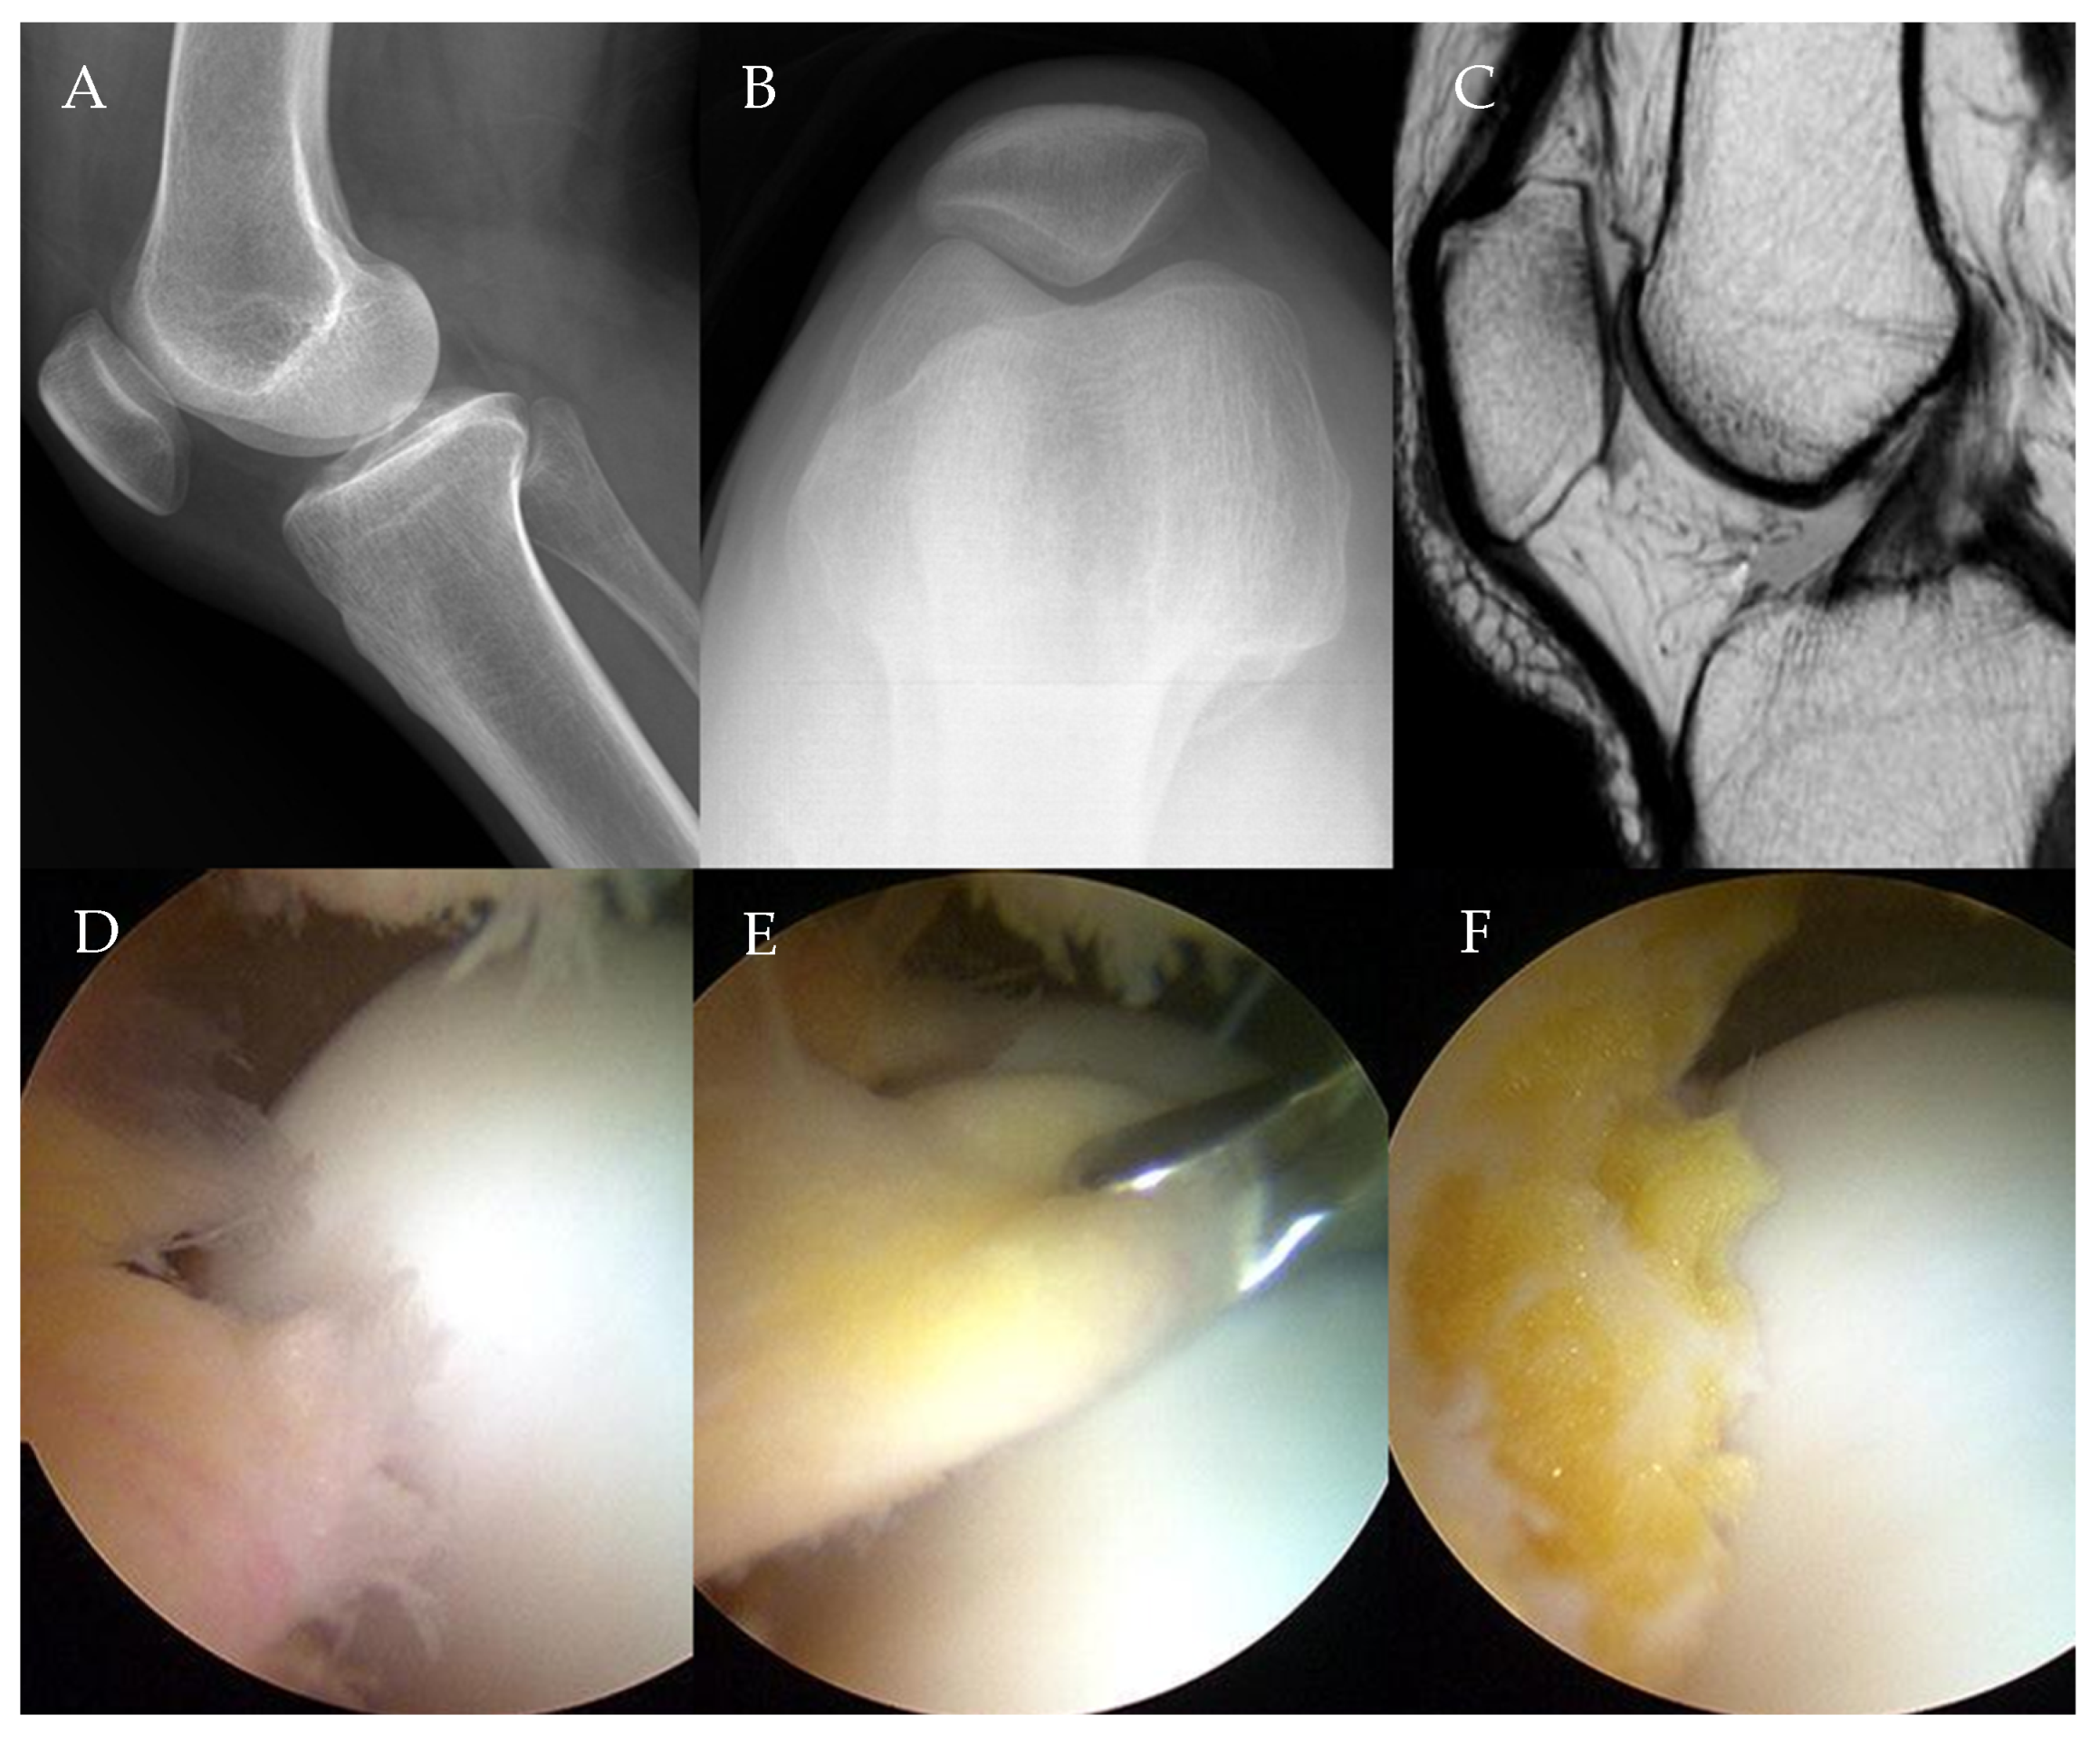

Of the 18 patients, 11 received partial and 7 underwent subtotal arthroscopic resection of the infrapatellar fat pad due to impingement syndrome (Figure 1).

Figure 1.

A 46-year-old female patient complaining of anterior knee pain of VAS 6 points that did not improve despite conservative treatment for more than 6 months. (A) Lateral knee radiograph showing an Insall–Salvati ratio of 0.98. (B) Merchant view showing K-L grade 0. (C) MRI showing infrapatellar fat pad volume of 656.24 mm2 and inflammatory and edematous changes. (D) Arthroscopic finding showing infrapatellar fat pad impingement. (E) Resection of the infrapatellar fat pad with a basket. (F) Infrapatellar fat pad after arthroscopic subtotal resection.